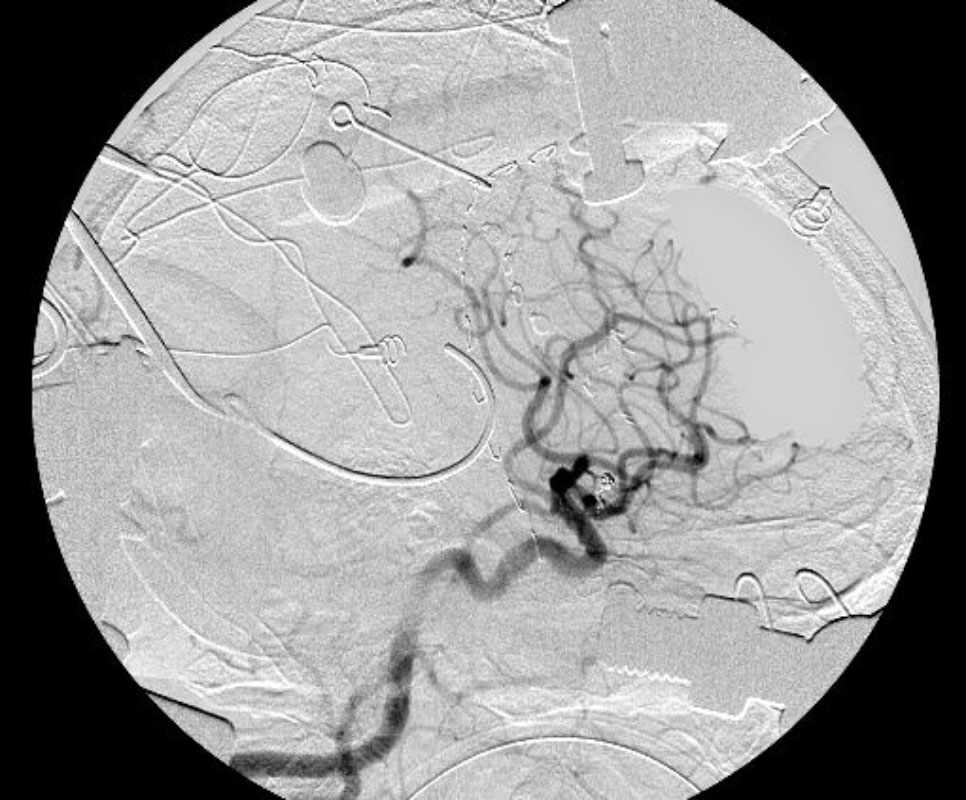

'19年5月

30代

富永/久貝

右中小脳脚 出血再発

SM 3(S1,E1,V1)

米国の病院

No.359 モニタリング

No.359 手術前

No.359 手術中

No.359 手術後

出血既往があり。2回の手術前血管内手術の後に、

Lateral transpeduncular approachにより再々出血予防を目的に

摘出手術を行う。完全摘出であることを確認した。

手術による合併症や後遺症なしで退院した。経過良好。